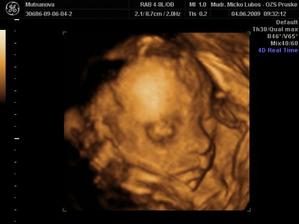

Naše druhé zlatíčko